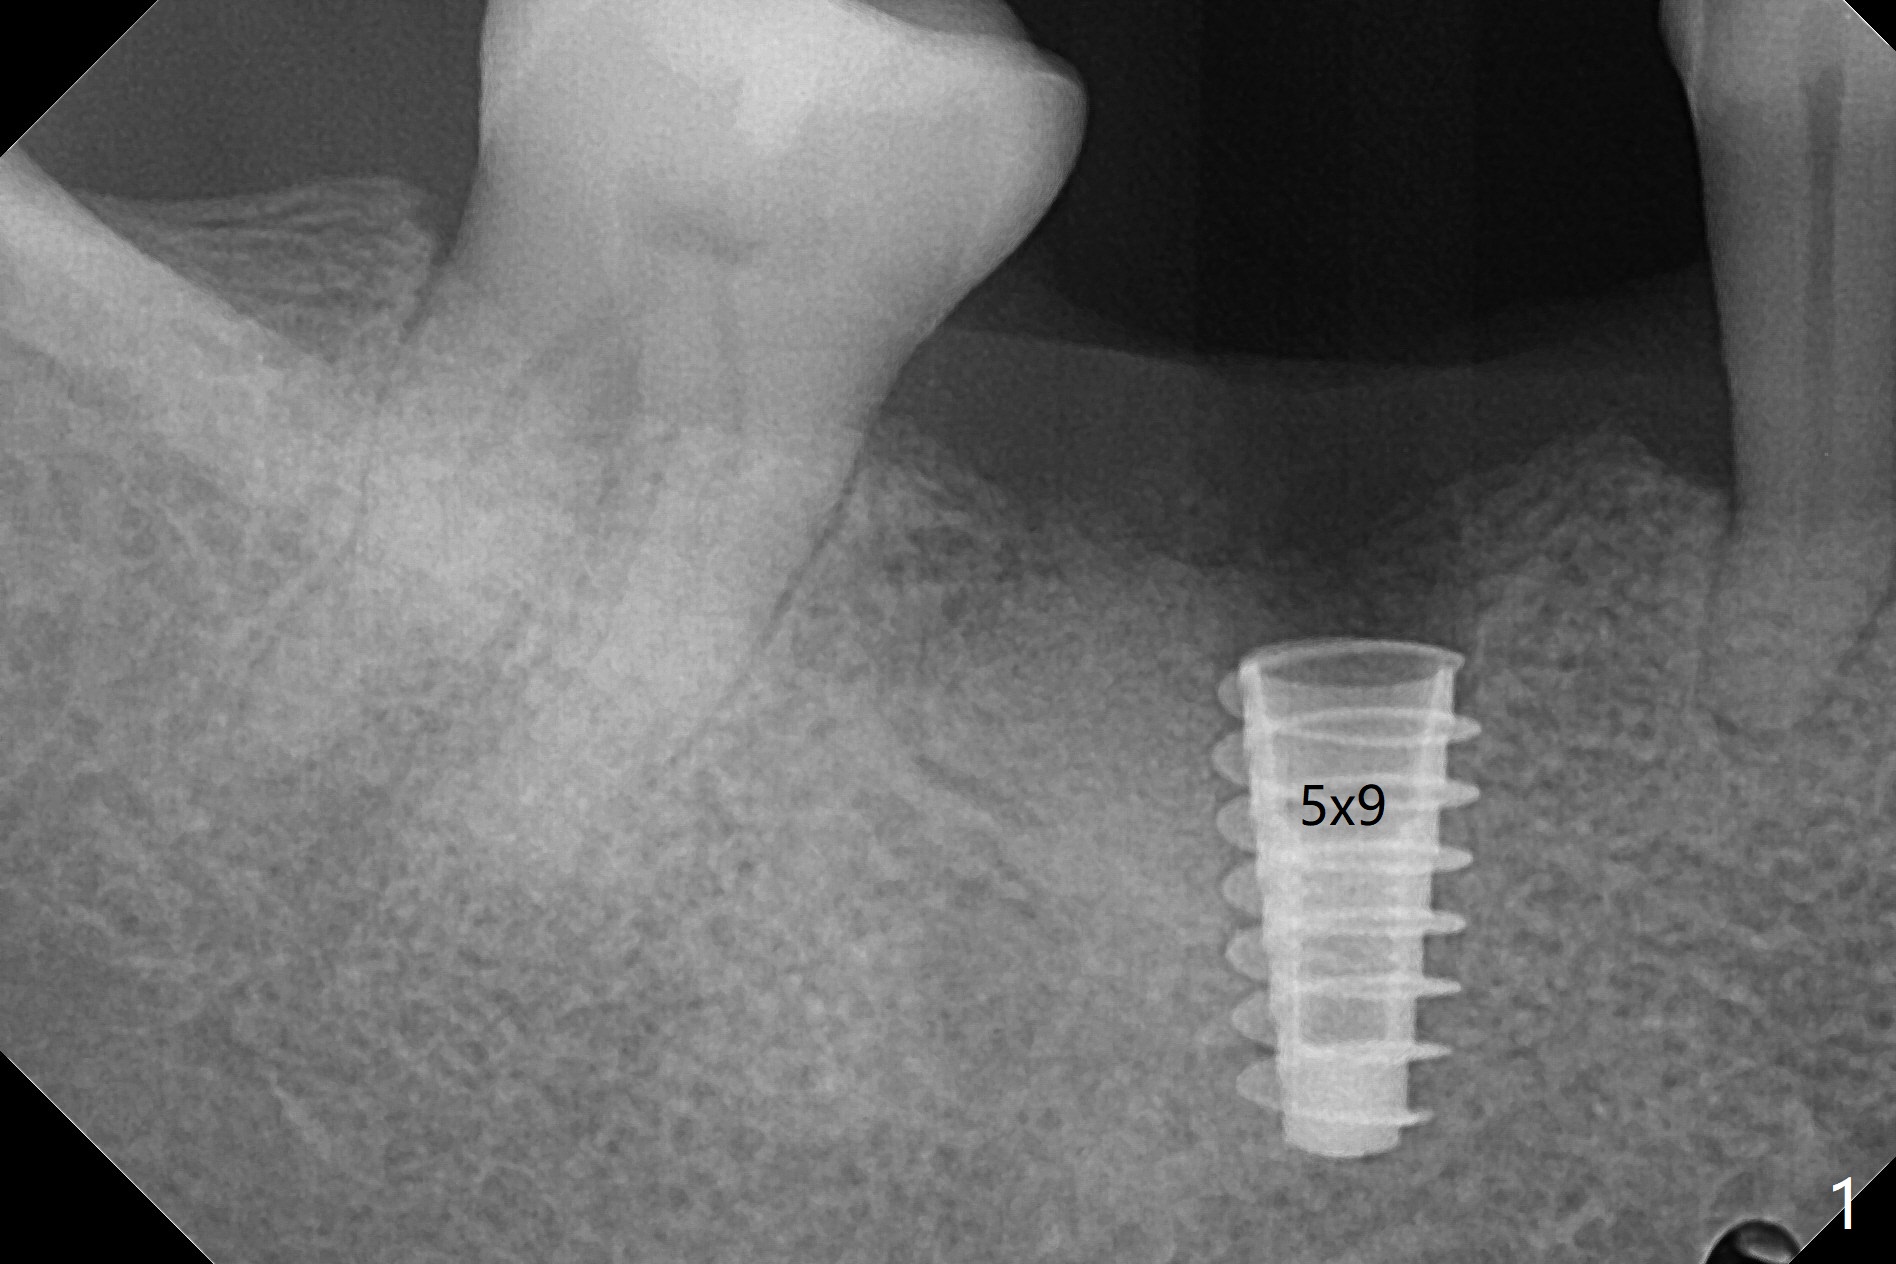

植体取出植骨后十个月,几乎按照导板顺序(除了4.5x10, 4x11.5毫米钻头),植入5x9毫米植体第二条线上缘,植体舌侧好像在牙槽嵴上(图一),临床上植体偏舌侧。放置愈合帽后,置入自体骨,往舌侧塞(图二:*),覆盖GEM Cap,牙周胶水固定,最后牙周敷料。其实植体舌侧偏移不是太多。